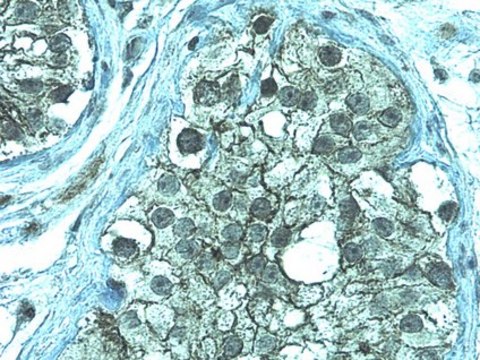

Immunohistochemistry Analysis: 1:500 dilution from a previous lot detected ZO-1 in normal human testis tissue.